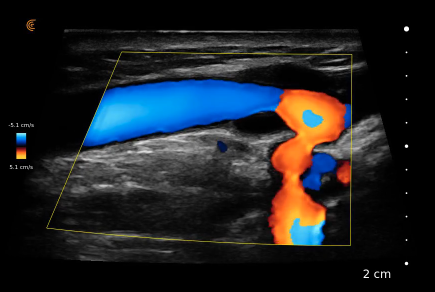

Visualize em cores e em tempo real a diferenciação entre as estruturas anatômicas. Tenha medidas automáticas e diversos recursos de otimização de imagem como o aprimoramento na visualização da agulha.

Modos: B, B/M, Color, PDI, PW, T-Mode, Elastografia